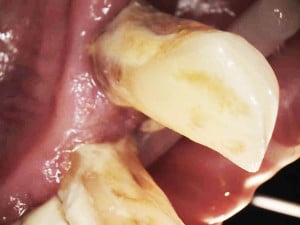

Na drugiej wizycie przeprowadzono dokładną kontrolę pozabiegową. Oznaczono ponownie wszystkie wskaźniki notując znaczną poprawę – API 17%, PBI 33%, sprawdzono głębokość kieszonek i ruchomości zębów.

Płytkę bakteryjną stwierdzono tylko w jednęj przestrzeni, krwawienie w dwóch, niektóre kieszonki spłyciły się. Niestety pani odłożyły się nowe złogi kamienia przy zębach siecznych. Przeprowadzono dokładny instruktaż szczotkowania i nitkowania, dobrano dla pacjentki odpowiednie środki do codziennej higieny jamy ustnej: szczoteczki międzyzębowe , pasty, płukanki, nici oraz skierowano dalej do periodontologa w celu przeprowadzenia dokładnego badania głębokości kieszonek i ewentualnego zabiegu root planingu .